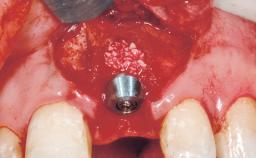

Immediate Flapless Placement of an Implant in a Maxillary Left Central Incisor Site

Type of Implants One-Piece

Placement Protocol Immediate implant placement

Tooth Site Maxillary incisor or canine

Socket Integrity Damage to one or more bone walls

Bone Volume Damage to one or more socket walls